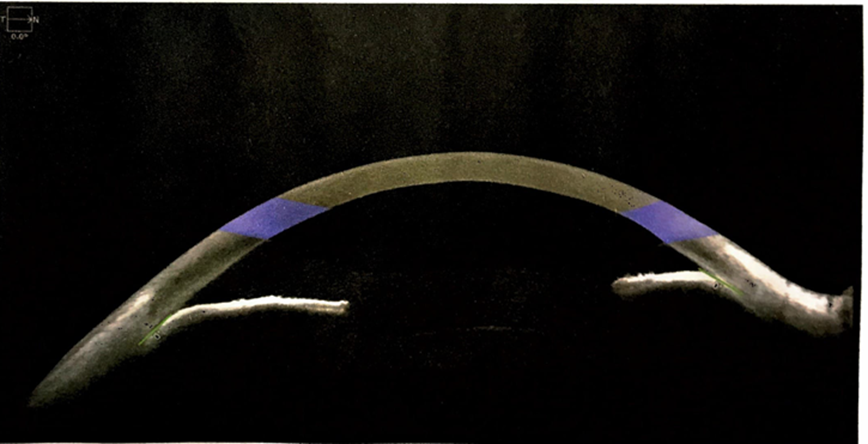

Investigations further confirmed disease progression. Optical coherence tomography of the optic nerve head and anterior chamber angle revealed changes consistent with glaucoma in the right eye (fig.2) and left eye is normal (fig.3). Humphrey Visual Field testing showed severe visual field loss in the right eye. Fundus Photo showing Full cupping in Right eye and normal cup disc ratio in left eye (fig.4). Pachymetry indicated a thinner cornea in the right eye, suggesting endothelial dysfunction. Laboratory investigations demonstrated elevated inflammatory markers, including ESR (42), CRP (11.4), and ANA (4.46). Additional tests, including TB Gold, HLA-B27, and VDRL, were negative, and urine analysis showed slight turbidity but was otherwise within normal limits. (table.2).

Fig. 2. Right Eye AS-OCT showing Iridocorneal angle closure

Fig. 3. Left eye AS-OCT showing normal Iridocorneal Angle